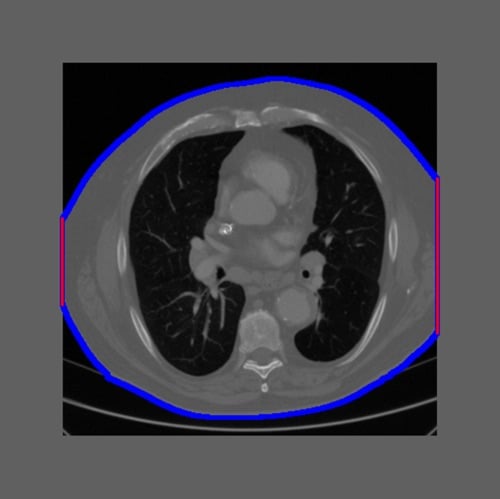

Figure 1: Example of an intentionally truncated CT image. The truncation percentage was calculated as the ratio of the patient border touching the field of view to the total patient border (red/(read+blue)). Image courtesy of Qaelum.

Our research team performed a study to investigate the effect of image truncation on the calculation of water equivalent diameter for chest and abdomen CT scans. We used a set of CT examinations (286 thorax and 222 abdomen CTs) for which the middle slice was not truncated, and then we intentionally truncated the images up to 50 percent (Figure 1). Non-truncated WED values were compared to truncated values.